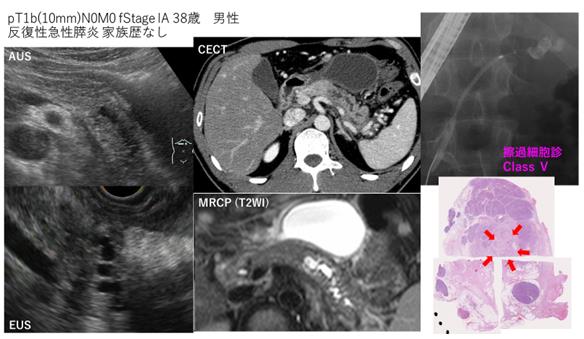

该患者因反复发生急性胰腺炎而被怀疑患有胰腺癌,我被送往医院。检查显示胰腺中的肿瘤为10mm,胰管也扩张。

可以从胰腺尾部的胰管扩张中发现胰腺癌

如果胰管突然扩张,您可以怀疑在扩张开始的区域发生了一些变化。在这张图片中,胰腺的真实部分消失,并被脂肪组织取代。在这种情况下,潜伏对应于胰管癌的前级细胞,癌细胞不再随着胰液流动,这应该由浸润来转移。通过CT进一步详细研究这种胰腺,胰腺的轮廓发生变形。即使存在这种异常,也可以认为在变形轮廓的部分发生了一些变化。

具体而言,我们通过CT / MRCP /超声波内窥镜等定期确定残留的胰腺是否有肿块,胰管扩张等。